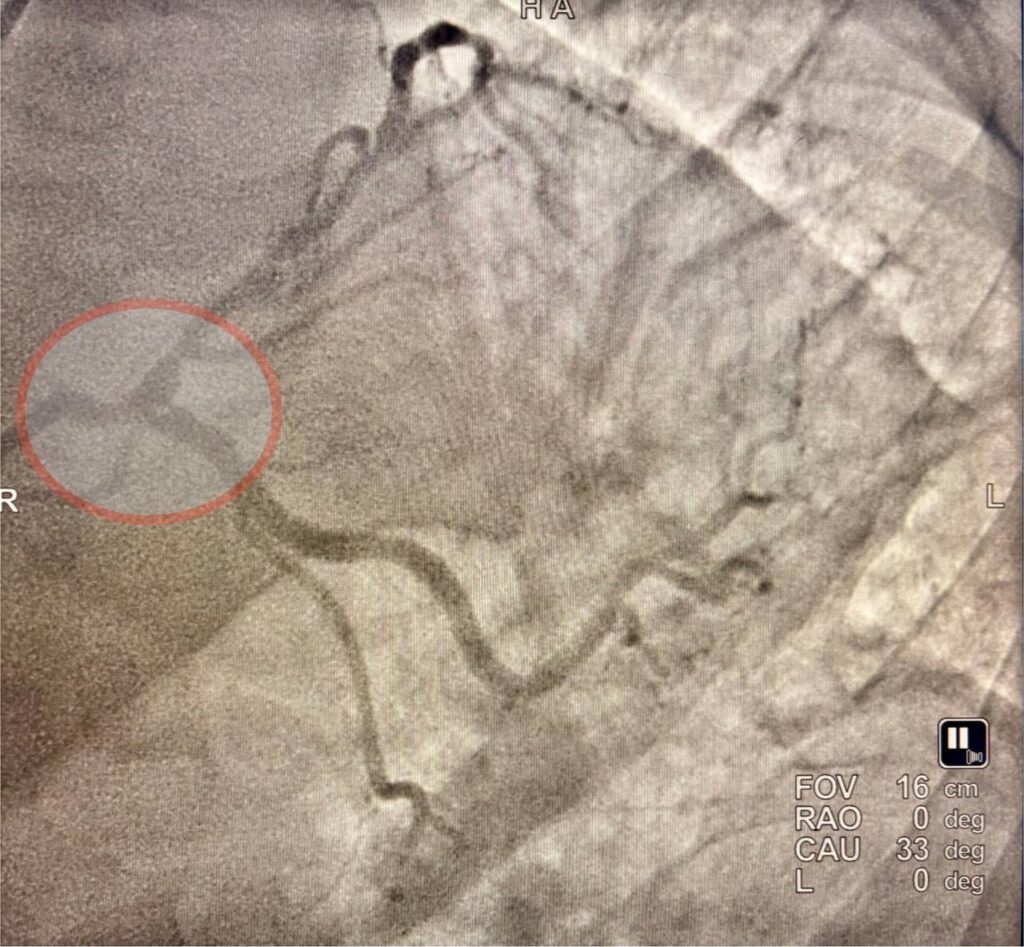

RIKIATM Qarshi filialida murakkab bifurkatsion shikastlanishli yurak tomirlari stentlash amaliyotlari muvaffaqiyatli bajarildi.

Respublika ixtisoslashtirilgan kardiologiya ilmiy-amaliy tibbiyot markazi Qarshi filiali intervension kardiologiya jamoasi tomonidan yana bir muhim va hayotiy ahamiyatga ega bo‘lgan murakkab operatsiyalar amalga oshirildi. Jamoa ikki nafar yurak qon-tomir kasalligi bilan og‘rigan bemorlarda bifurkatsion shikastlanishli koronar tomirlarni stentlash bo‘yicha yuqori texnik mahorat talab etuvchi murakkab amaliyotlarni muvaffaqiyatli o‘tkazishdi. Birinchi holatda bemorda chap koronar arteriya o‘zagi […]